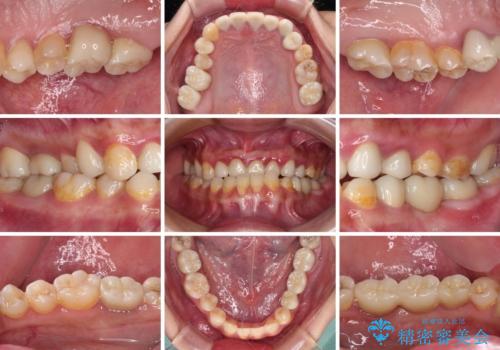

むし歯だらけの奥歯 セラミッククラウンによるむし歯治療

- 奥歯のむし歯を気にして来院された患者様です。

痛みのある歯が多く、根管治療が必要と診断されました。

左下の歯は、クラウンを装着するために必要な高さが足りないため、歯冠長を延長するための外科処置を行うこととしました。

根管治療や歯周外科処置後にフルジルコニアクラウンにて補綴治療することとしました。

自身の口腔内への意識が高くなく、汚れが非常に多い方でした。

再発や他の歯がむし歯となるリスクを低減させるため、日頃からのプラークコントロールと定期的なクリーニングが重要となります。